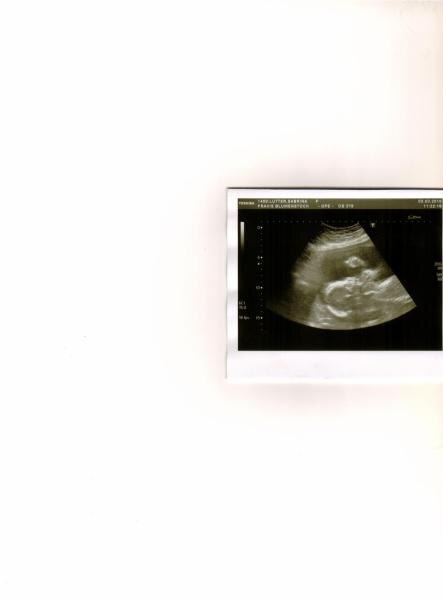

Also es ist alles bestens,mein Schätzchen wiegt rund 390 gramm,größe weiß ich nun garnicht upps. Aber es ist 100% ein Junge und alles supi.Mein Blutdruck war heute 100 zu 80. Und was mein hoher Blutdruck im stehen oder bei der Arbeit wäre,solle ich lieber erst nach der Entbindung klären lassen,ka warum,sie war heute sehr kurz angebunden. Er war ganz schön Aktiv und boxte was rum,hab mal ein Foto mit rein gestellt. Wünsche euch noch einen schönen sonnigen Tag. LG

Hi Du und erstmal herzlichen Glückwunsch, ist immer wieder schön zu erfahren das es den Zwergen gut geht :-). Das mit dem Blutdruck kenne ich. Bei der vorletzten Untersuchung hatte ich 140 zu 85 und diesmal 110 zu 65. So geht das bei mir die ganze Zeit, hoch und runter :-). Aber zu niedrigen Blutdruck bin ich schon vor der SS gewohnt. Das Foto ist ja total süß, süßes Gesicht. Schönen Tag noch, GLG Kerstin